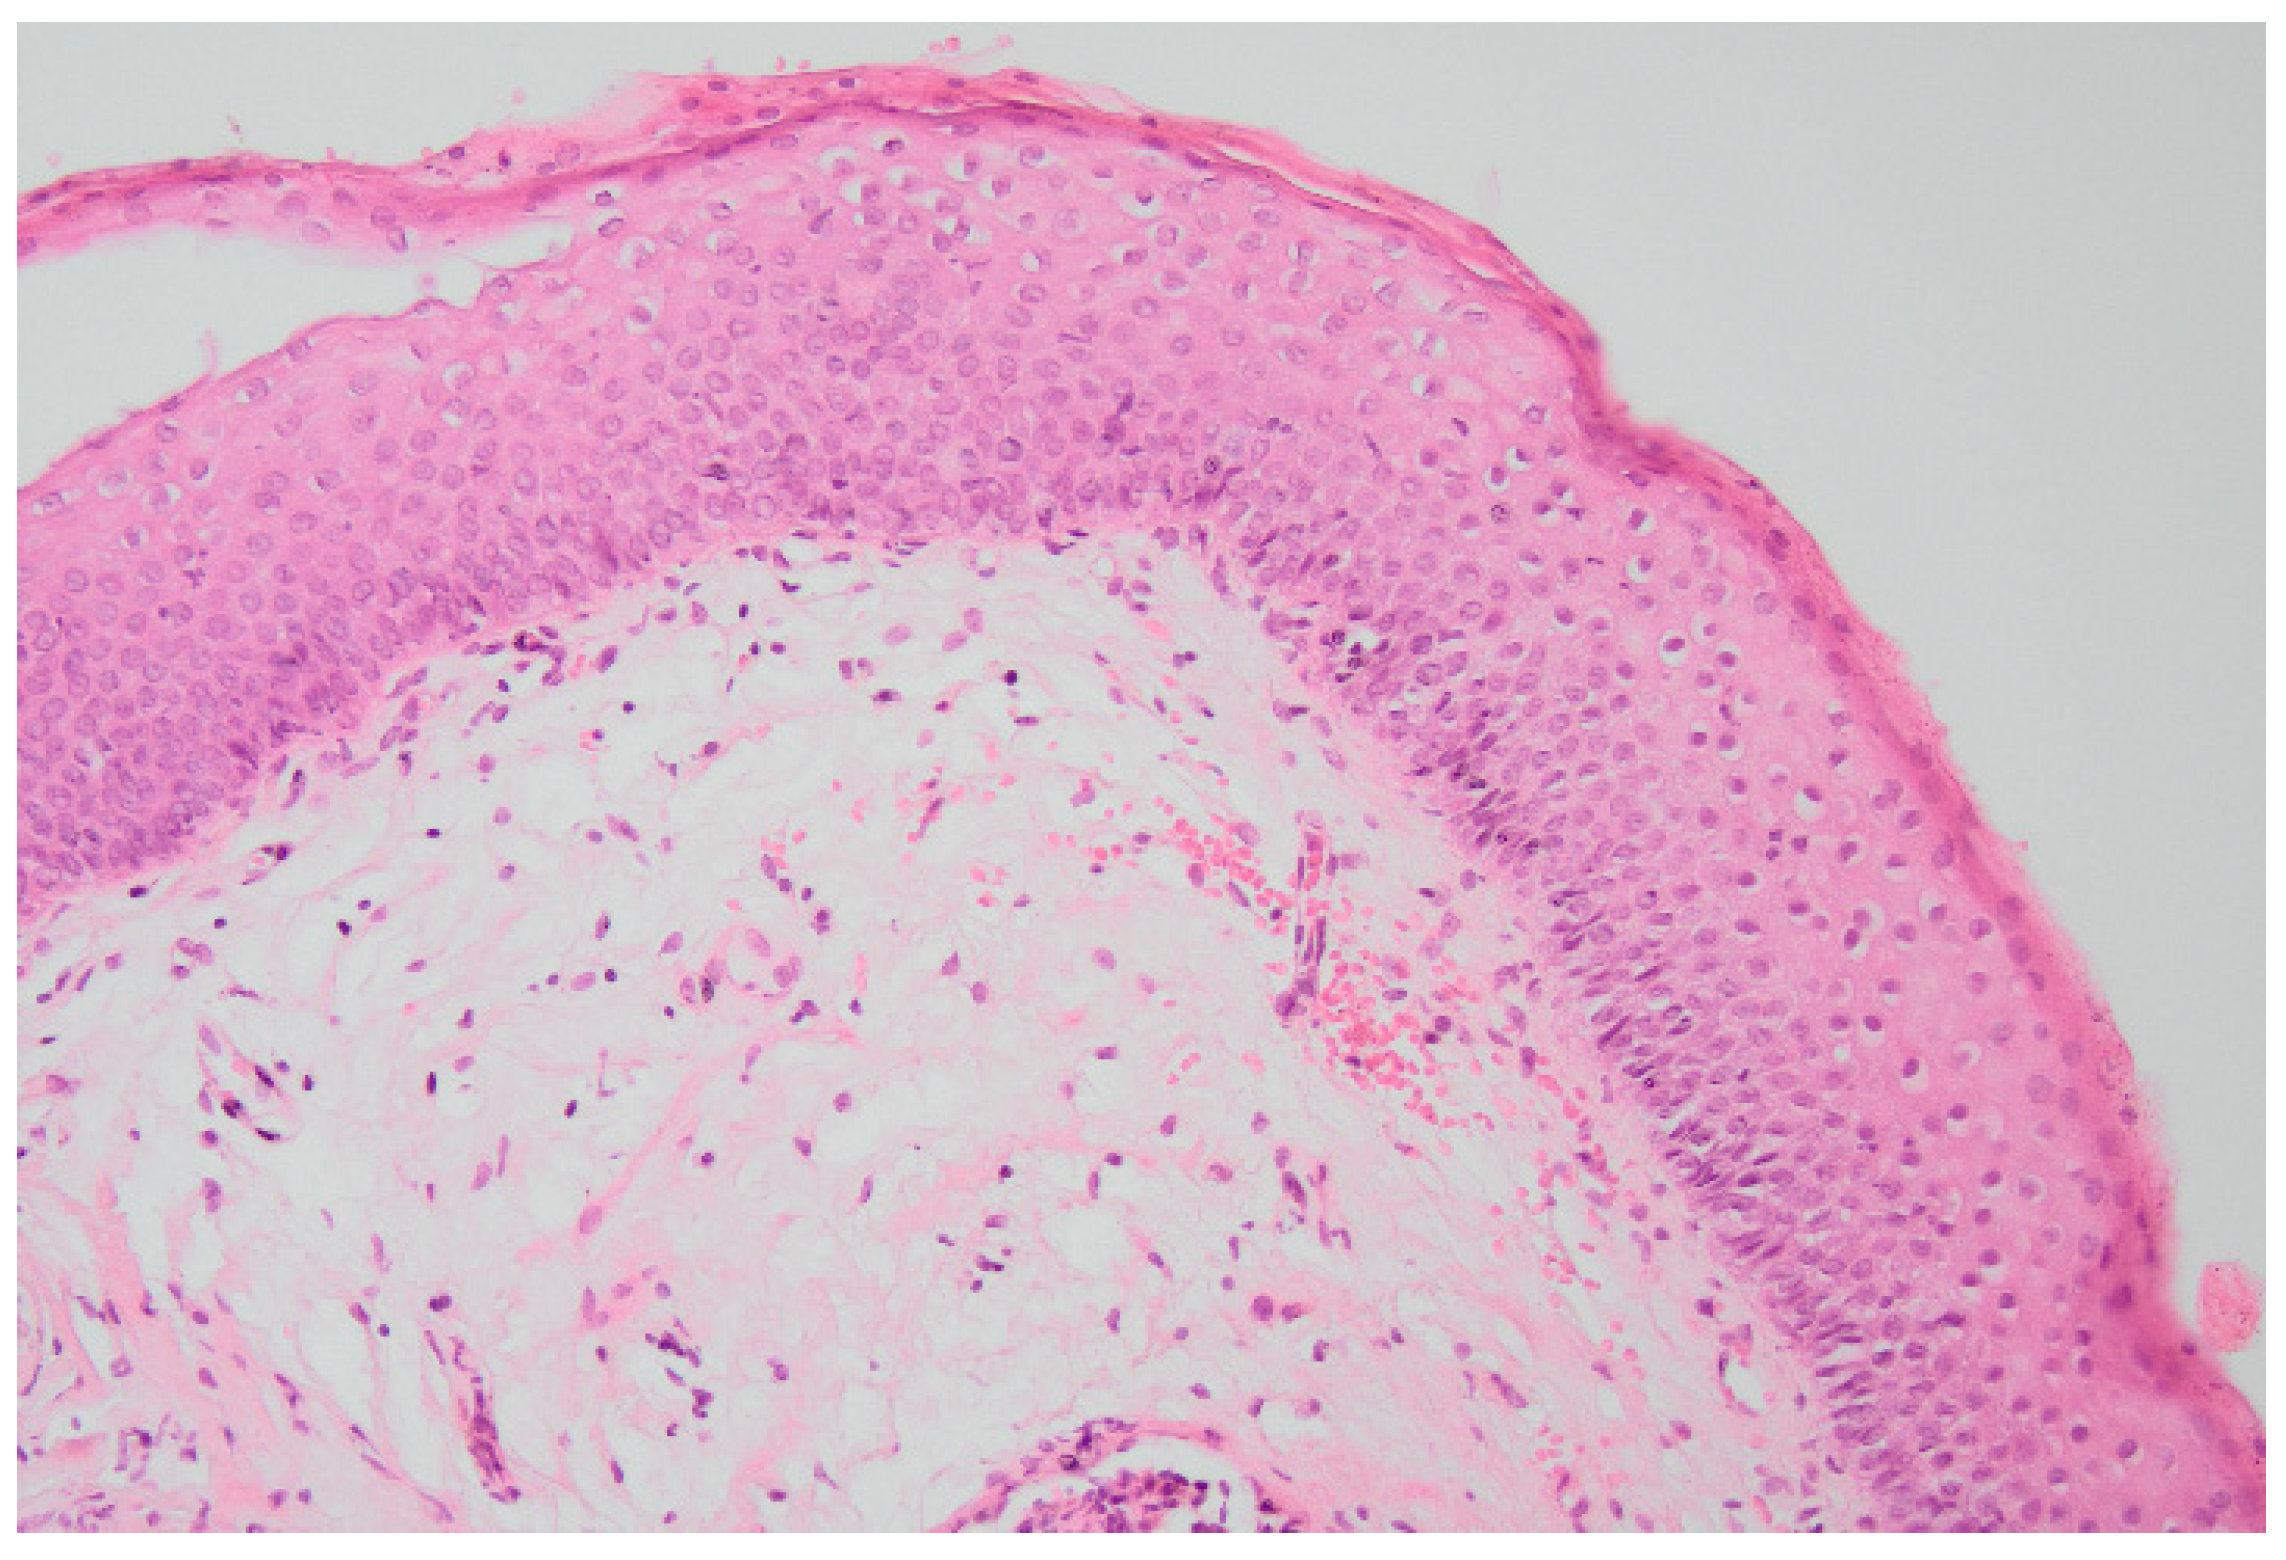

| 1B | 12 | Increased sensation in the bladder. High maximal pressure in the bladder during micturition. | Reactive changes in the urothelial epithelium and underlying florid proliferation of von Brunn’s nests |

| 2B | 17 | Not tested | Segmental non-keratinized squamous metaplasia without inflammatory infiltrates |

| 3B | 14 | Mild detrusor overactivity with increased sensation in the bladder | Slight chronic inactive inflammation of the urothelial epithelium with reactive changes and focal squamous non-keratinized metaplasia |

| 4B | 13 | Normal | Moderate chronic active inflammation and swelling of the urothelial epithelium with reactive changes |

| 5B | 17 | Increased sensation in the bladder with reduced bladder capacity. Lower urinary tract dysfunction with urgency sensors. | Focal chronic active inflammation of the urothelial epithelium with reactive changes of the urothelial epithelium and focal non-keratinized squamous metaplasia |

| 6B | 14 | Increased sensation in the bladder with reduced bladder capacity. | Moderate chronic active inflammation of the urothelial epithelium and non-keratinized squamous metaplasia |

| 7B | 17 | Increased sensation in the bladder with reduced bladder capacity. | Chronic inactive inflammation of the urothelial epithelium and visible non-keratinized squamous metaplasia |

| 8B | 18 | Detrusor overactivity with increased sensation in the bladder. Reduced bladder capacity. | Non-keratinized squamous metaplasia * |

| 9B | 17 | Urethral flow with bladder obstruction features. | Non-keratinized squamous metaplasia |

| 10B | 13 | Urethral flow with bladder obstruction features. | Reactive changes of the urothelial epithelium and underlying florid proliferation of von Brunn’s nests |

| 11B | 16 | Detrusor overactivity with increased sensation in the bladder. Reduced bladder capacity. | Normotypic urothelial epithelium with swelling of the stroma and sparse infiltrates of lymphoid cells |

| 12B | 14 | Detrusor overactivity with increased sensation in the bladder. Decreased bladder capacity. | Normotypic urothelial epithelium with swollen and bloodshot stroma |

| 13B | 16 | Detrusor overactivity with increased sensation in the bladder. Reduced bladder capacity. | Non-keratinizing squamous metaplasia |

| 14B | 17 | Detrusor overactivity with increased sensation in the bladder. Reduced bladder capacity. | Non-keratinized squamous metaplasia with poor lymphocyte infiltrates |

| 15B | 13 | Detrusor overactivity with increased sensation in the bladder. Reduced bladder capacity. | Non-keratinized squamous metaplasia and cystitis glandularis |

| 16B | 14 | Detrusor overactivity with increased sensation in the bladder. | Focal active inflammation of the urothelial epithelium and focal non-keratinized squamous metaplasia |

| 17B | 17 | Detrusor overactivity with increased sensation in the bladder | Focal chronic inactive inflammation of the urothelial epithelium and squamous non-keratinized metaplasia |